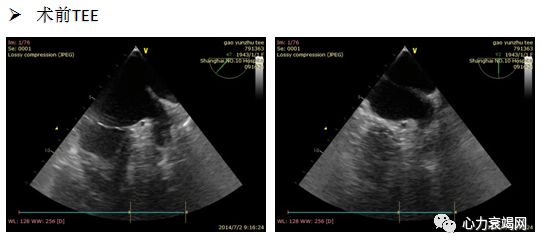

TTE:LA内径 54mm,LVEF 61%,微量心包积液

TEE:LA后前径55mm, LAA2叶, 开口内径19 mm, 深度24mm